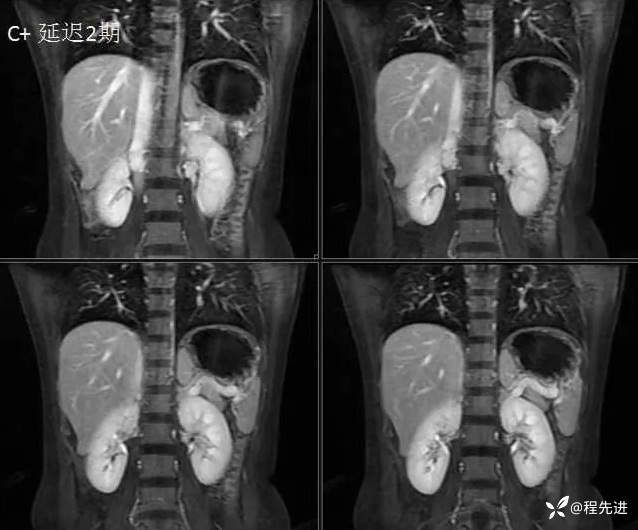

MRI检查: